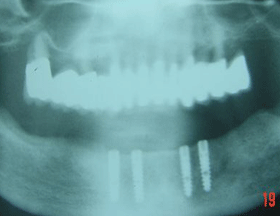

This X-ray shows 4 CAMLOG implants placed in the lower jaw.